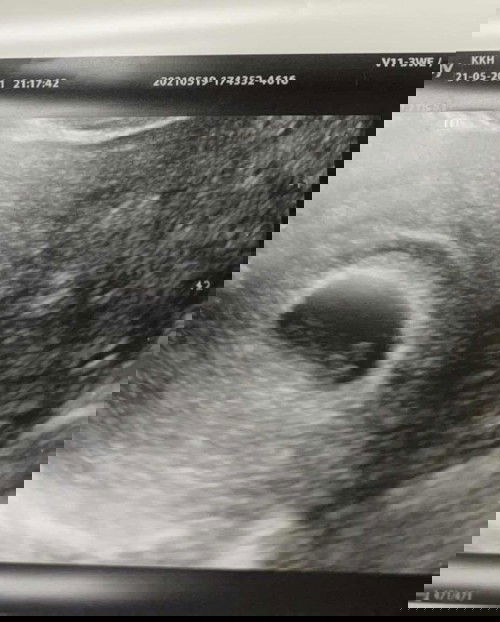

Bleeding at 8 weeks

Im a first time mom and been bleeding lightly for 7 days now. Today I went A&E and doct said still cant find baby (there is sac and baby yolk). And baby should be 6 weeks instead of 8zz My previous scan which showed blood clot above the sac has also cleared. Do I have hope mummies? Anyone experienced the same? Im very anxious